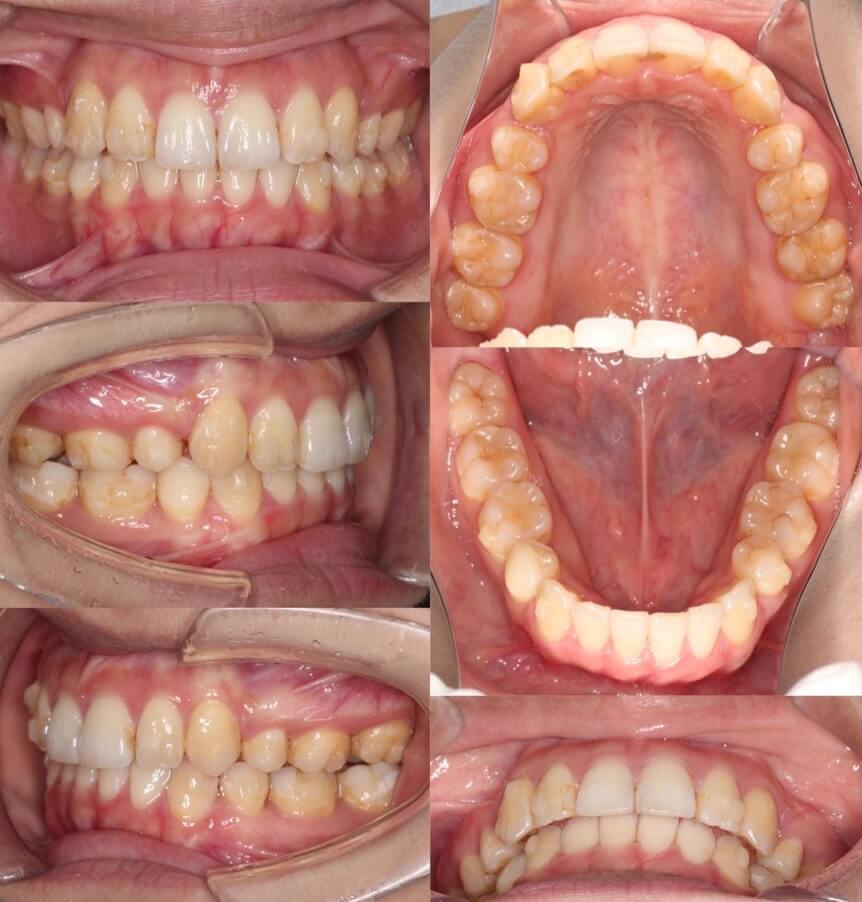

「美容目的にはリスクが伴う」

20代女性・マウスピース型装置・美容改善型

上の前歯の角度もE-lineも悪くはないのですが、患者さんは横顔での口元の突出感を改善したいということで、マウスピース型装置にて上下小臼歯抜歯矯正治療を行いました。美容目的要素が強くなるため、ほうれい線が深くなったり、ブラックとライアングルが増えるリスクについては事前によく説明しています。治療結果は前歯の後方移動量に対して横顔の変化量は少なめとなり、ちょうど良い形になりました。

<症例概要> 難易度:★★★☆☆

主訴:出っ歯・横顔の突出

年齢・性別:30代女性

住まい:千葉県船橋市

症状:軽度叢生・下顎前歯唇側傾斜

治療方針:抜歯空隙の閉鎖(中等度固定)

治療装置:マウスピース型矯正装置(アライナー装置)

抜歯:上下左右4番(計4本)

治療期間:1年6か月

アライナー枚数:47+30ステージ

リテーナー:上下クリアタイプ+フィックスタイプ

治療費用:990,000(税込)

代表的副作用:痛み・治療後の後戻り・歯根吸収・歯髄壊死・歯肉退縮